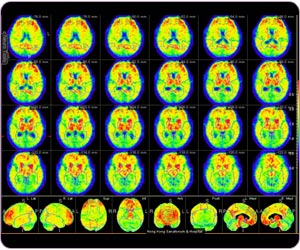

C-11 PIB PET detects typical Alzheimer's disease with amyloid plaque at post cingulate gyrus, frontal lobe, precuneus, parietal lobe and temporal lobe.

C-11 PIB PET MIP: Alzheimer disease

Region-based quantitative analysis for C-11 PIB brain study